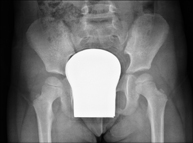

- RX Pelvis

Procedimiento mediante el cual, utilizando rayos X, se obtienen imágenes de la pelvis para su estudio, especialmente de los huesos pélvicos.

- RX Caderas pediatría

Estudio que, utilizando los rayos X, permite obtener una imagen de los huesos de la cadera y descartar luxaciones.